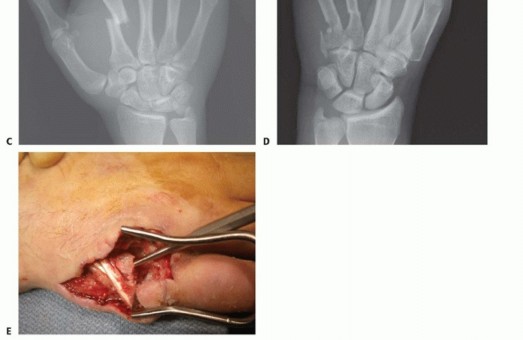

Standard radiographic imaging forms the cornerstone of diagnostic evaluation, requiring, at minimum, a dedicated posteroanterior (PA), a true lateral, and a pronated oblique view of the injured hand. The PA view is excellent for assessing coronal plane angulation and transverse displacement, though it notoriously underestimates sagittal plane deformity. The true lateral view is critical for quantifying apex-dorsal angulation, though overlapping metacarpal shadows can complicate interpretation. The pronated oblique view often provides the clearest visualization of the fracture profile and the degree of comminution.

When standard radiographs are equivocal, or when dealing with complex intra-articular fractures and suspected CMC fracture-dislocations, advanced cross-sectional imaging is mandatory. High-resolution Computed Tomography (CT) with 3D reconstructions provides unparalleled detail of articular step-offs, occult comminution, and the precise spatial orientation of fracture fragments. This information is invaluable for determining the feasibility of lag screw fixation versus the necessity of bridge plating. Furthermore, obtaining radiographs of the uninjured, contralateral hand serves as a vital anatomical template, allowing the surgeon to accurately gauge the patient's native metacarpal length and intrinsic diaphyseal curvature.

Clinical & Radiographic Imaging Archive